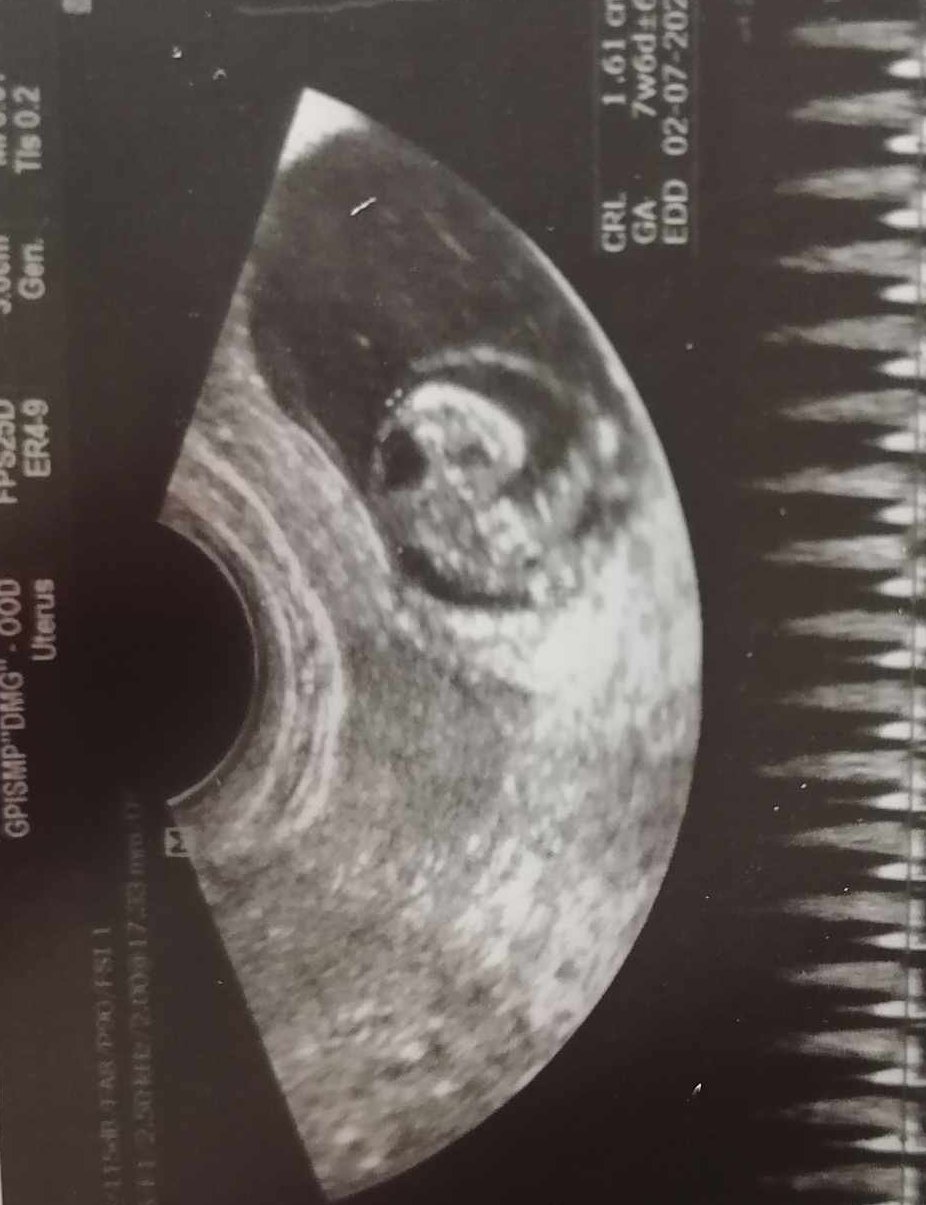

Аз напоследък започнах по-често да усещам гадене. Връхлита ме извендъж, става ми зле на стомаха, прималява ми, дояжда ми се. Ако не хапна нещо, имам чувството, че ще повърна. Спасява ме чист бял хляб от това състояние. Лесна уморяемост и аз имам. По цял ден предпочитам да съм в леглото, защото всичко ме изморява. Утре съм на АГ да види как са нещата /сега съм 7 г.с. + 4 дни/ и силно се надявам малкото човече да се развива нормално.